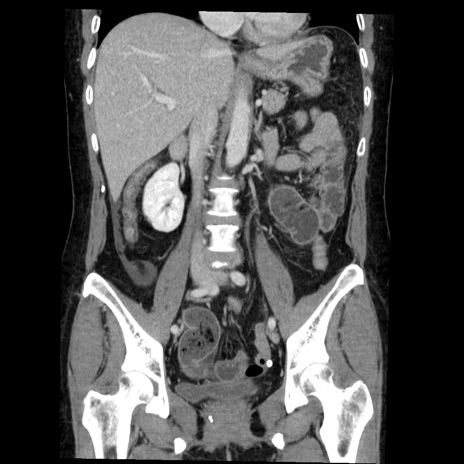

症例6(冠状断像)

【症例】50歳代女性

【主訴】下腹部痛

【現病歴】本日朝より下痢2回あり。 昼食を食べた後、嘔吐3回、下腹部痛認め、症状軽快せず、当院救急搬送。

最終食事:本日昼(生ものなし)。 昨日の夜、刺身を食ぺたとのこと。周囲に同様の症状の者なし。普段、排便は毎日あるとのこと。

【既往歴】卵巣癌術後(8年前に当院で卵巣摘出)

【身体所見】 意識清明、腹部:平坦、腸蠕動音→、やや硬、下腹部自発痛・圧痛あり、反跳痛あり、筋性防御なし。

【データ】WBC 16000、CRP 0.01